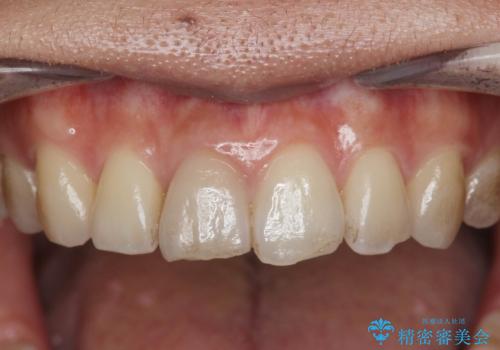

- 変色してきた前歯の形態回復、色調の改善を求めて来院されました。

X線検査、歯髄(歯の神経)の検査を行ったところ、失活(歯の神経の死んだ状態)であると診断されました。